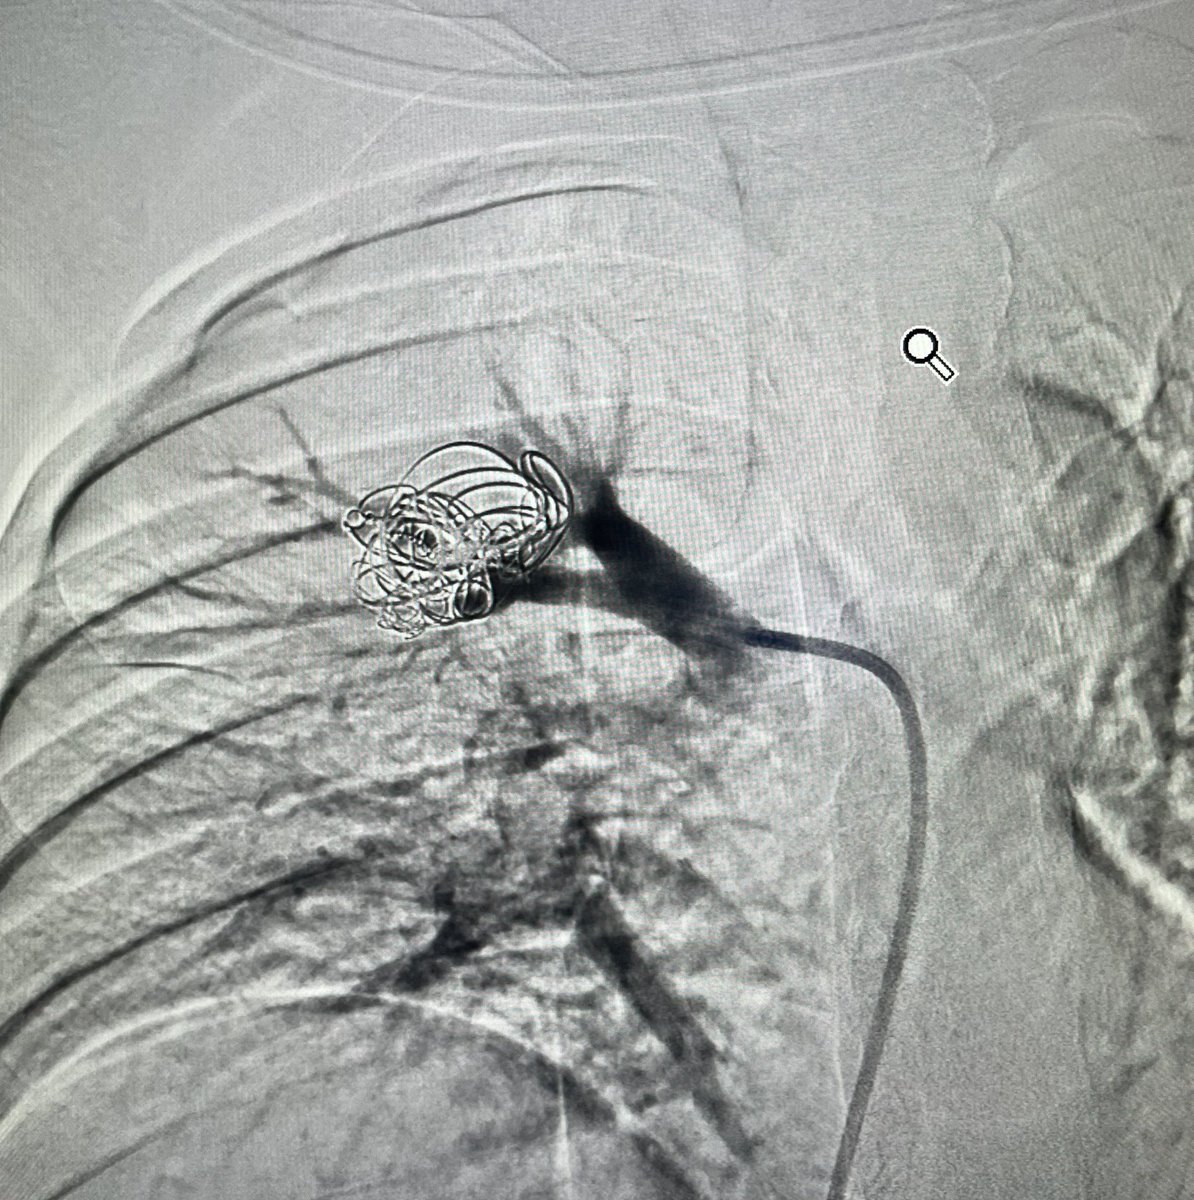

Lower GI Cecal bleeding, scope failed to manage, superselective coil embolization was performed. Hematochezia stopped. Inotropes were off.